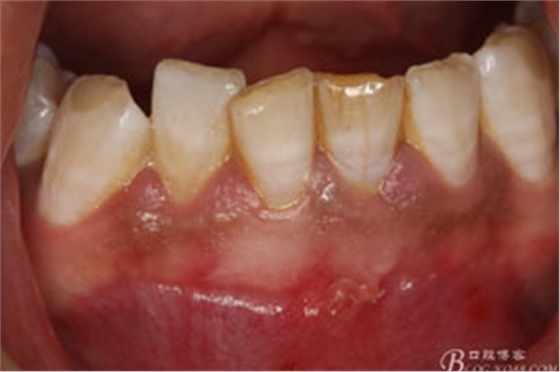

1.患者術(shù)前的口內(nèi)照片:31唇側(cè)有一膿瘺。捫診溢膿。